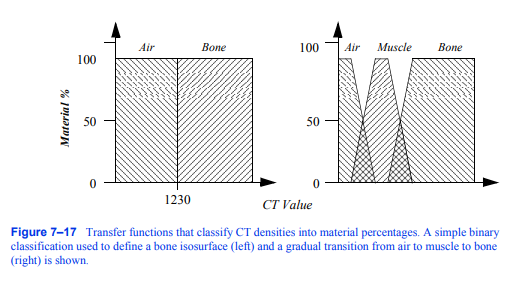

对数据集中感兴趣的相关对象进行分类是生成大量渲染图像的关键步骤。这些信息用于确定物体对图像的贡献,以及物体的材料属性和外观。例如,通常通过指定密度阈值来对CT数据集中的数据样本是否对应于骨骼进行简单的二进制分类。当体素上的标量值大于此阈值时,将其分类为骨,否则将其视为空气。这本质上是在空气和骨骼之间的过渡体积中指定了一个等值面。如果我们把这个操作画在所有可能的标量上,我们会得到

图7-17将CT密度划分为材料百分比的传递函数。一种简单的二元分类,用于定义骨等值面(左)和从空气到肌肉再到骨骼的逐渐过渡

(右)所示。

即图7 - 17中左边所示的二进制步进函数。在体绘制中,我们把这个函数称为传递函数。传递函数负责将体素位置上的信息映射为不同的值,如材质、颜色或不透明度。体绘制的优势在于它可以处理比二进制步进函数复杂得多的传递函数。这通常是必要的,因为数据集包含多种材料,分类方法不能总是以100%的概率将单一材料分配给样本。利用先进的图像分割和分类技术,可以将单个组分体积处理成多个材料百分比体积[Drebin88]。回顾我们的CT示例,我们现在可以指定一个材料百分比传递函数,定义从空气到肌肉,然后从肌肉到骨骼的逐渐过渡,如图7 - 17右侧所示。